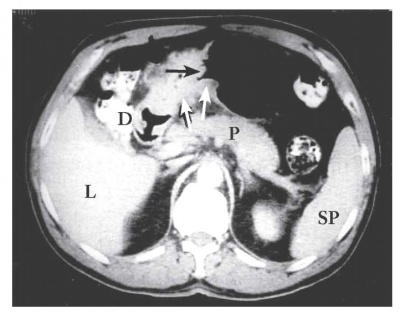

טומוגרפיה ממוחשבת - מאפשרת להדגים את גודל השאת, התפשטותה לאיברים סמוכים, בלוטות לימפה מוגדלות או גרורות לאיברים אחרים (תצלומים 21.3-18.3). ב-CT הדיוק באבחנת T4 הוא 90% וב-T1 הוא 23%.